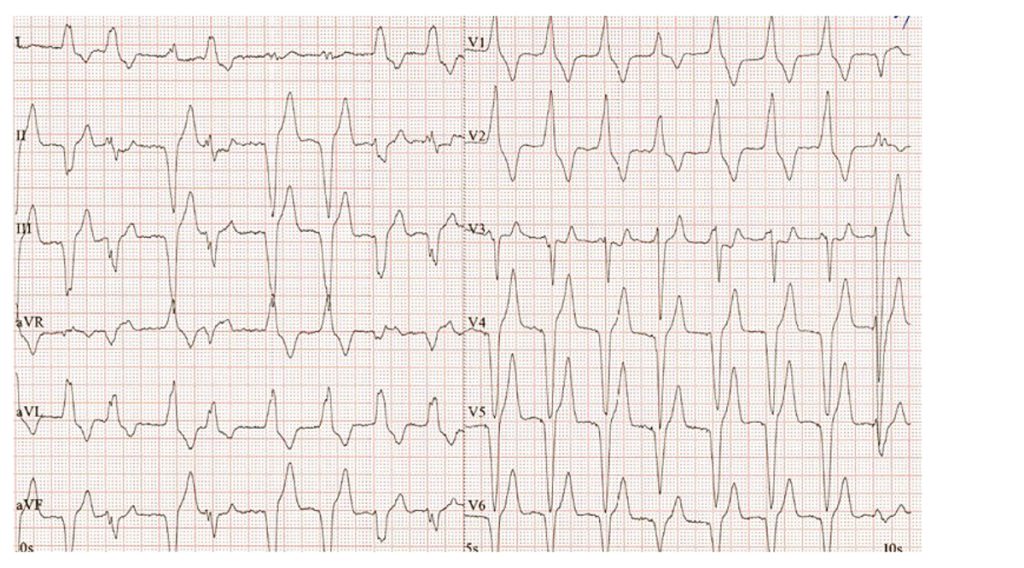

Obr. 3 EKG u pacienta se zhoršením srdečního selhání

Elektrokardiografie prokázala fibrilaci síní. Na obrázku je patrná komorová stimulace bez zřetelné pravidelné aktivity síní, se vzhledem blokády pravého Tawarova raménka a širokým QRS komplexem, četné komorové extrasystoly (obr. 3).